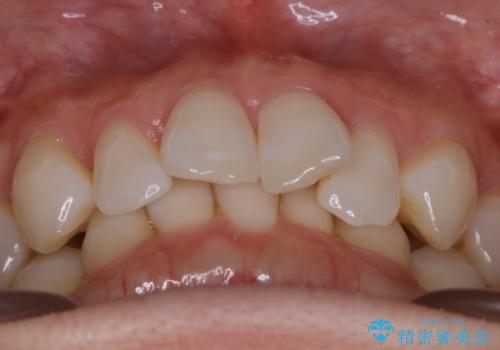

【抜歯】矯正治療とインプラントで正常な噛み合わせを実現

- 元々は矯正治療を主訴にご来院されました。

治療を始めるにあたり、精密検査を受けていただき全体の状況を把握したうえで矯正治療の計画を立てることとなりました。

その過程で左下の6番目の歯は治療が必要な状態であることが分かり、被せ物を外して内部を確認してみると根が破折してしまっていることが判明しました。

歯が深い位置で破折している場合は基本的には抜歯が選択されます。

様々な治療プランを患者さんと相談させて頂き、最終的にインプラントで噛み合わせを回復させていくこととなり、まず悪くなっている歯を抜歯することから開始しました。